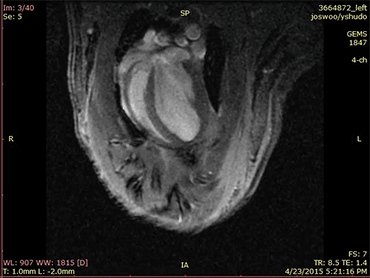

LIGHT HEARTED When exposed to light, photosynthetic bacteria (green) make oxygen that can keep rat heart cells (red, shown here growing in a lab dish) alive after a heart attack.

J.E. Cohen et al/Science Advances 2017